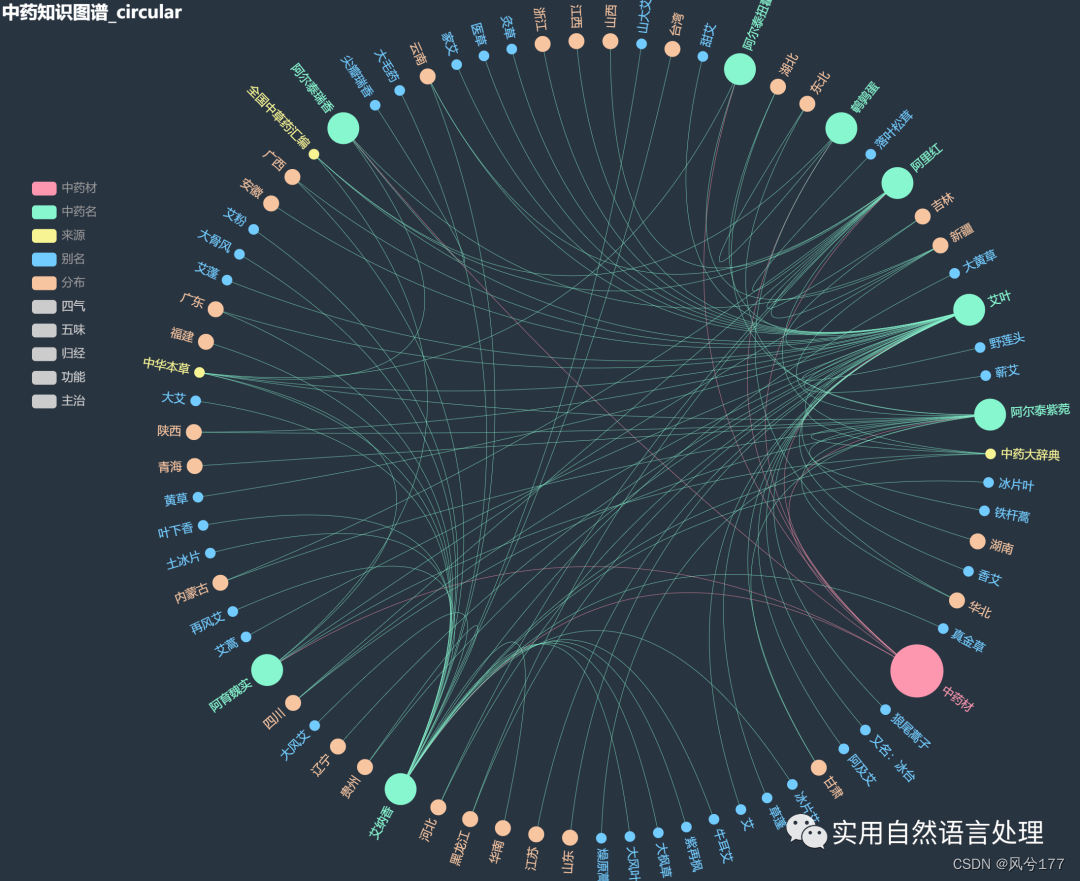

少量数据的中药知识图谱-环形图(部分节点展示图1)

少量数据的中药知识图谱-环形图(部分节点展示图2)

本文将基于pyecharts框架,对中药材知识图谱进行“力导图”和“环形分布”可视化,同时,对中药材地理分布、来源和别名关系进行分析与可视化。

2.2 中药材知识图谱可视化

前文自顶向下构建中药知识图谱初探已经介绍了中药材知识图谱的构建和neo4j可视化过程,接下来将对该图谱数据利用pyecharts进行可视化。